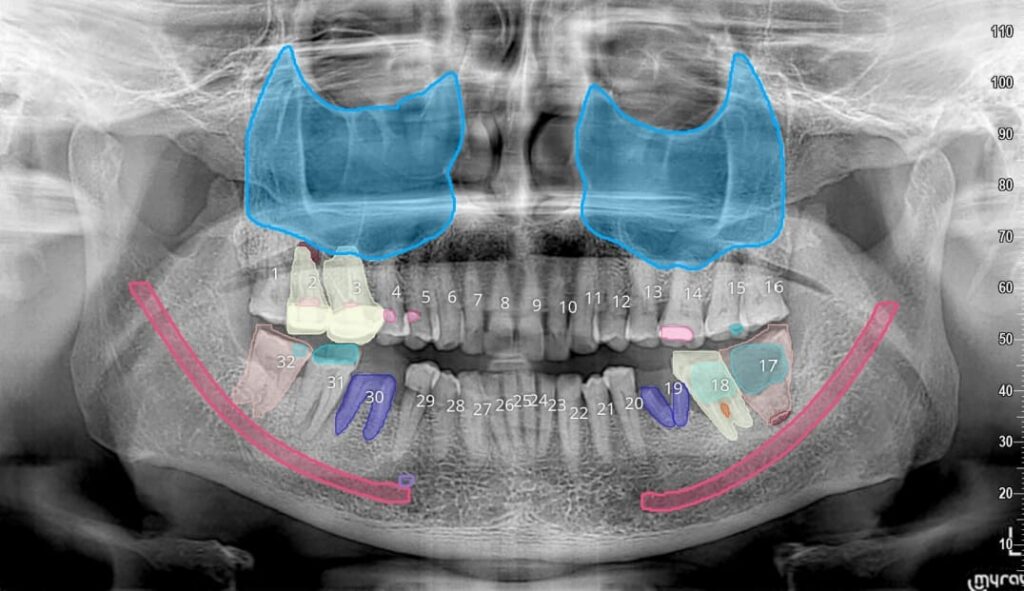

Pre-Implant Assessment

Post-Implant Assessment

Endodontic Assessment

Impacted Tooth

Pathology Assessment

OPG Reporting

Periodontal Assessment